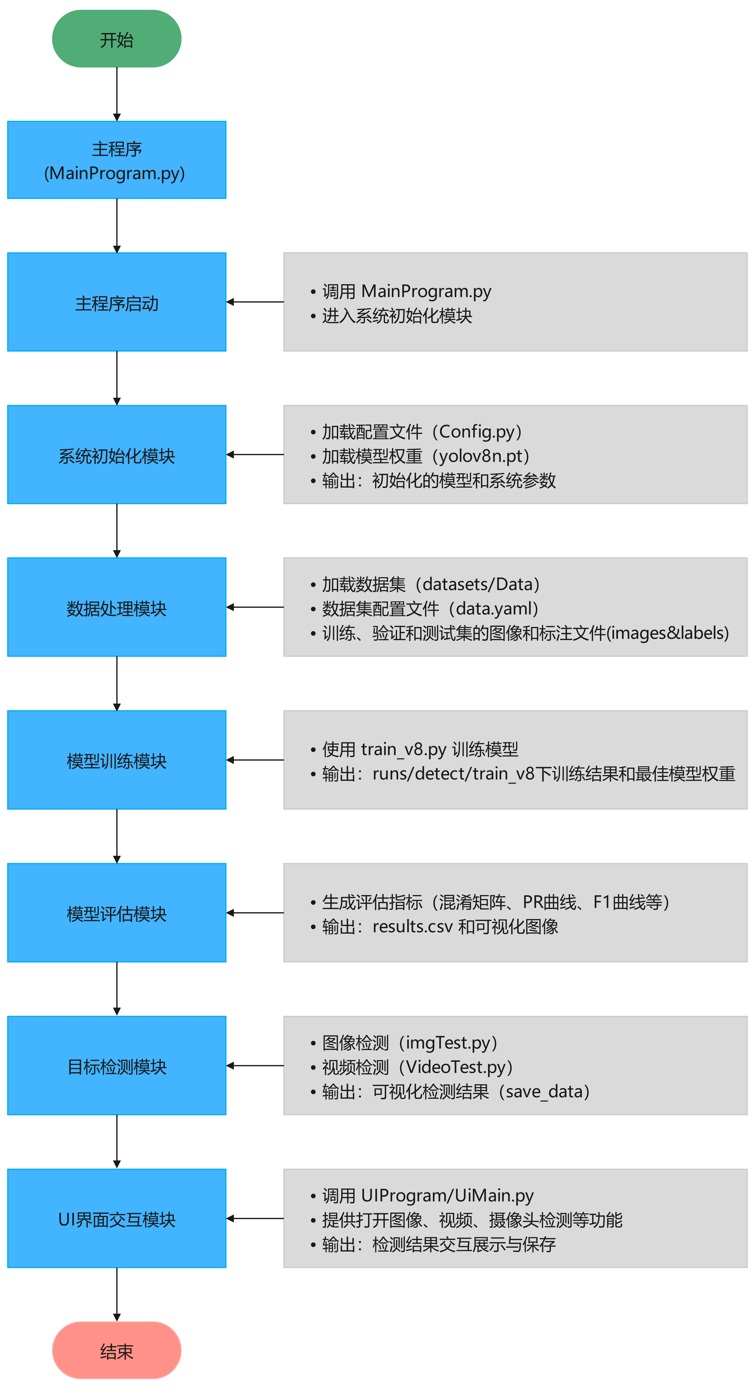

算法流程

Tipps:深入解析项目的算法流程,逐步探索技术实现的核心逻辑。从数据加载与预处理开始,到核心算法的设计与优化,再到结果的可视化呈现,每一步都将以清晰的结构和简洁的语言展现,揭示技术背后的原理与实现思路。